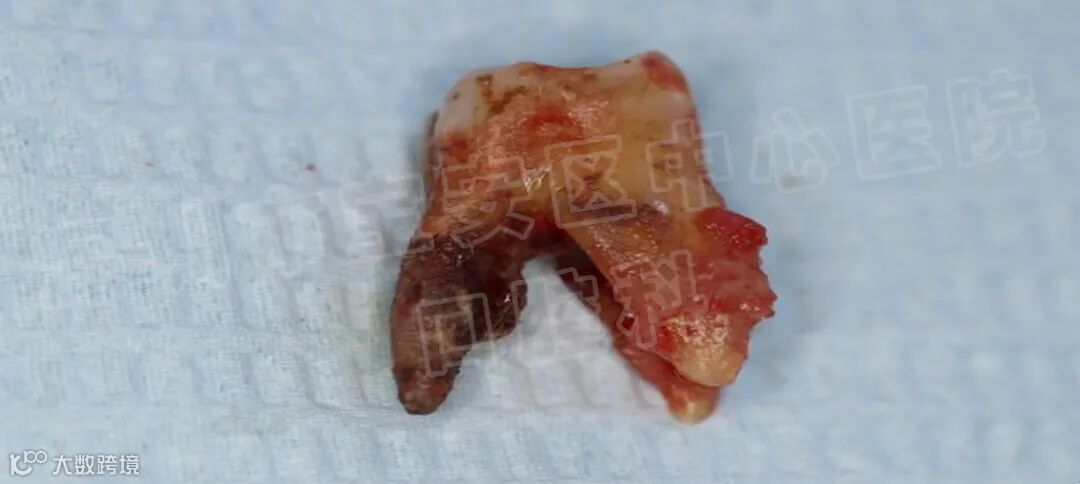

经过上述治疗之后,大多数患者的牙周炎症可以得到消除,松动的牙齿慢慢稳固,患者的咀嚼功能明显提高。但是,经过牙周基础治疗之后,部分患者仍然会有个别牙齿,甚至多颗乃至整个牙弓中的余留牙齿松动,难以行使正常的咀嚼功能,一旦出现上述问题,则需要采用牙周炎手术治疗。牙周翻瓣,牙周再生,骨再生等手术去恢复牙龈炎症,牙槽骨吸收等问题